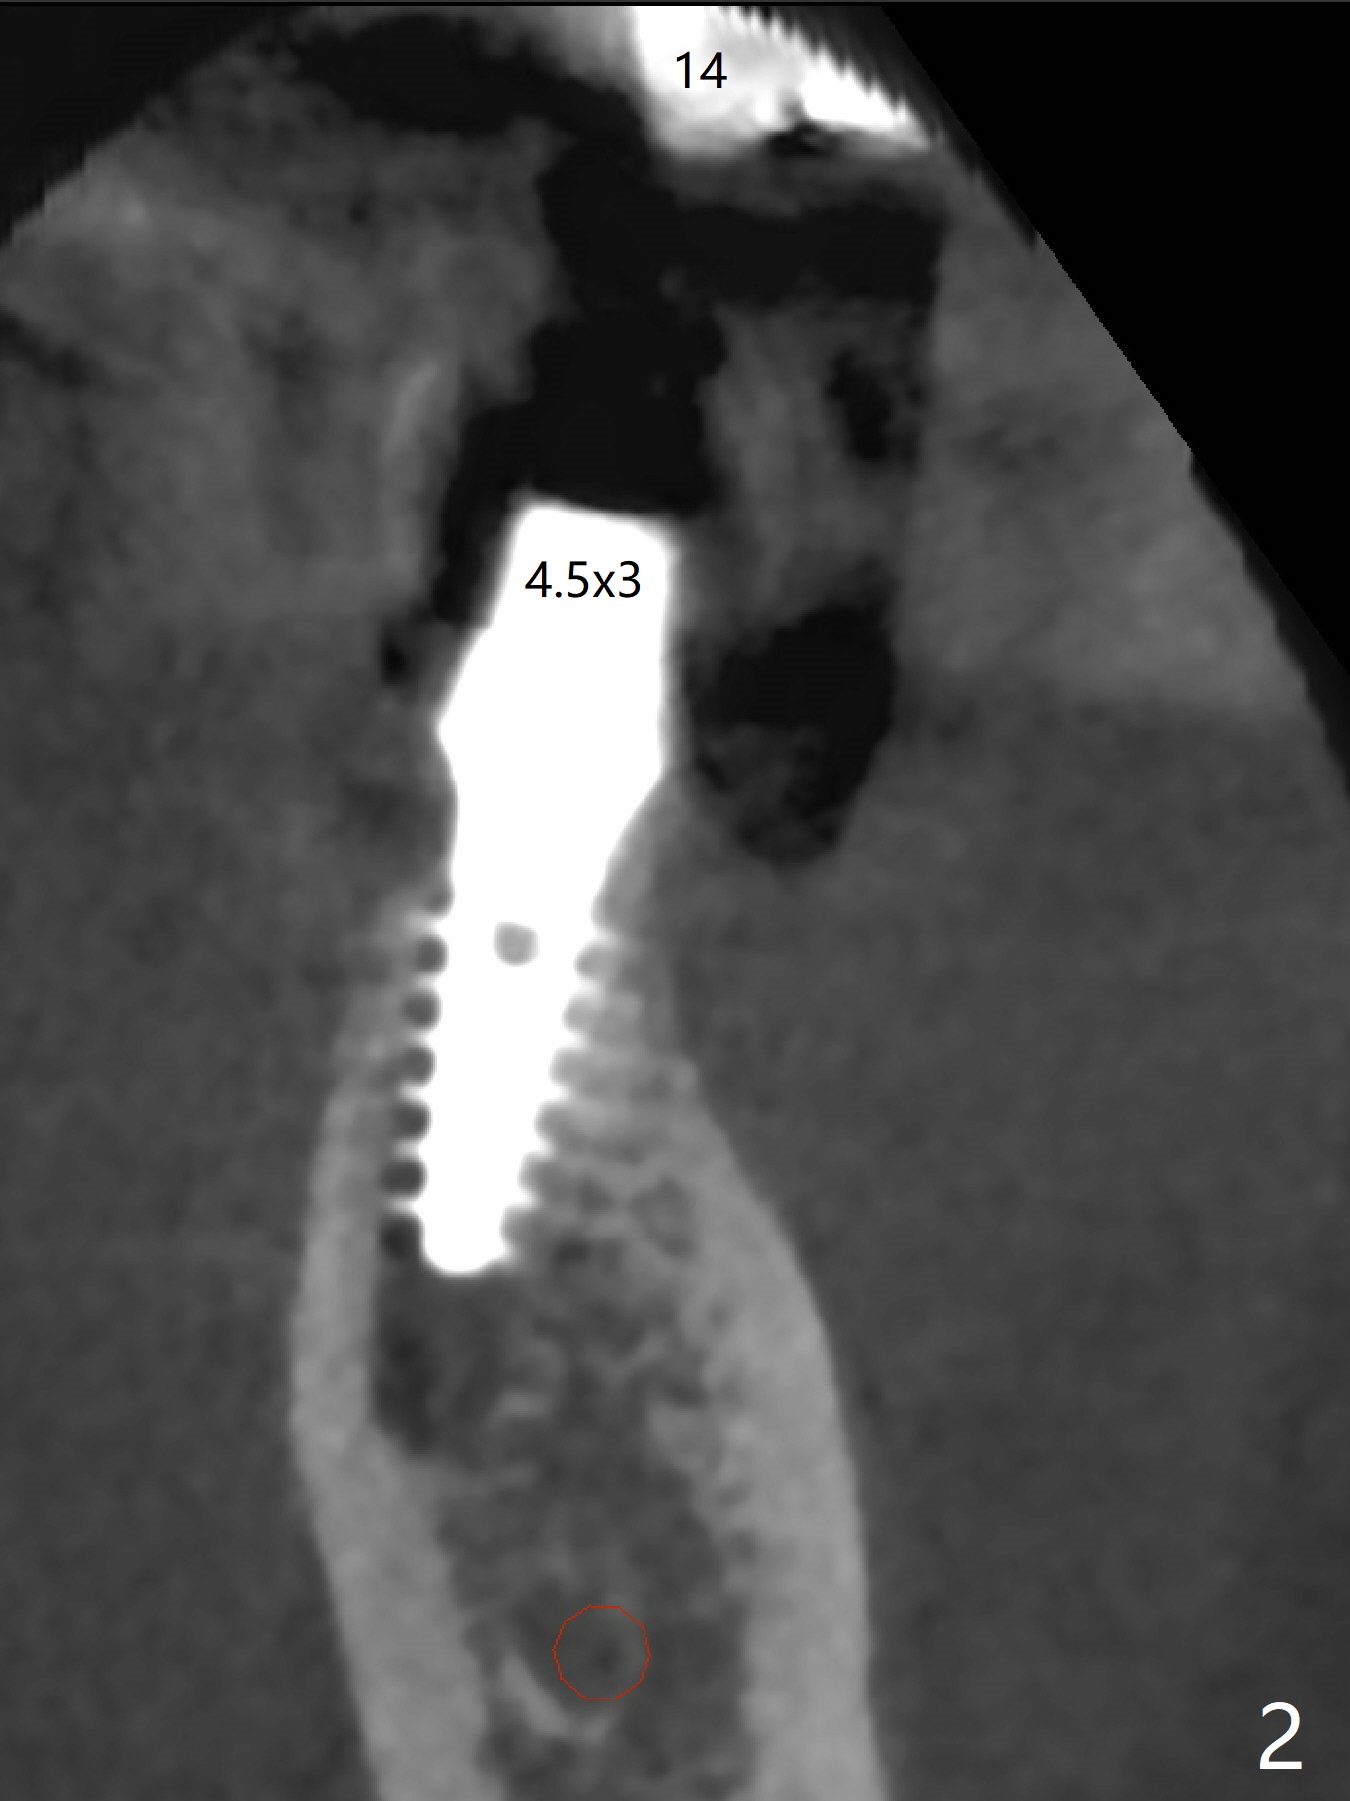

After finishing osteotomy at #19 according to IS drill sequence for 4x10 mm implant except cortical tap, a 4x9(2) mm Magicore is placed with ~ 50 Ncm (Fig.1). A 4.5x3 mm solid abutment is placed to check occlusion (Fig.2). There is discrepancy in osteotomy depth probably due to difference between the implant systems or overprep for subcrestal placement (narrow ridge, Fig.2 *). The implant could be 2 mm longer or the cuff could be longer (3 mm instead of 2 mm). The implant with 4.5x3 mm solid abutment is stable for impression nearly 3 months postop (Fig.3). Appreciate the distinct thread pattern of Magicore 3 months 1 week postop, immediately post cementation (Fig.4). Bone density increases 7 months post cementation (Fig.5 *). There is less likely implant fracture associated with a 1-piece one than a 2-piece one when a narrow one is placed in the narrow ridge.